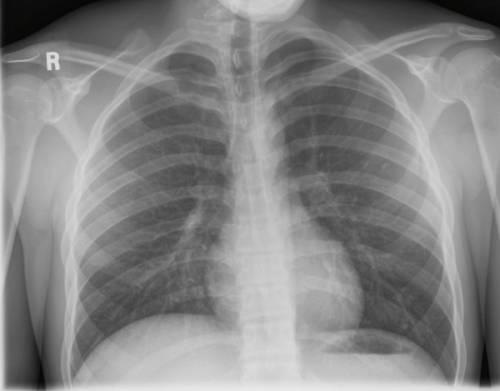

Tool to train medical student's eyes as to what a normal chest x-ray looks like, with over 500 consecutive normal images.